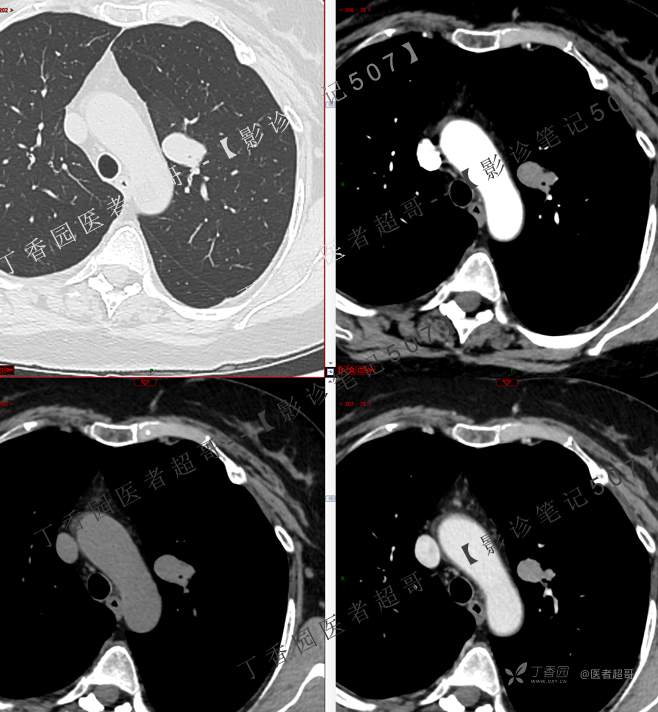

患者性别:女

患者年龄:50岁

简要病史:患者4月余前出现无明显诱因及病因出现胸痛,无咳嗽咳痰等表现。

小细胞肺癌 (54)